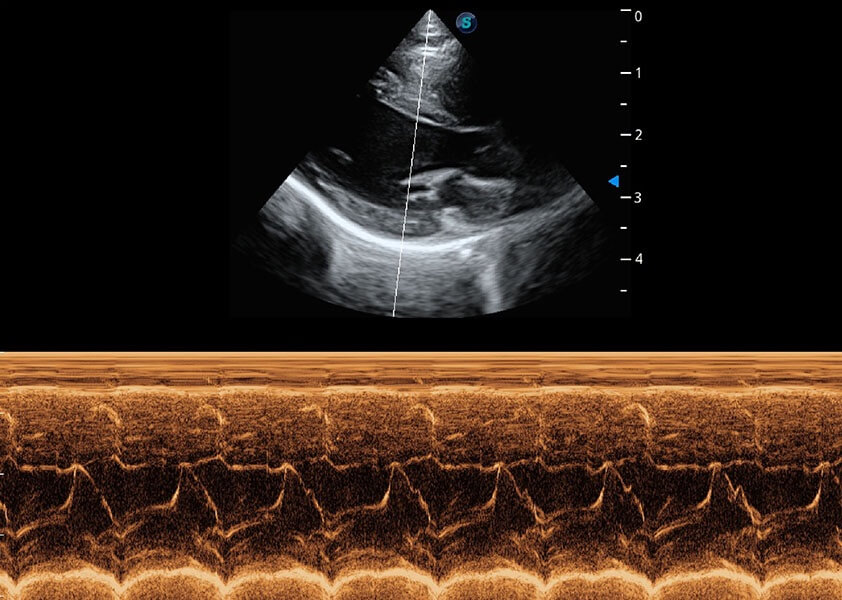

ProPet 60 作為一款高端臺式動物超聲設(shè)備,為動物醫(yī)生的日常診斷提供了一系列貼合動物臨床需求、解決臨床實(shí)際問題的高級成像功能。憑借全系列高清探頭,滿足醫(yī)生對腹部、心臟、生殖、淺表、肌骨等成像的所有需求,切實(shí)幫助您提升檢查效率,提高診斷信心。